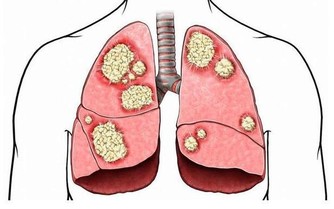

2. 增加你患癌症的風險

就像細菌讓你的牙齦腫脹一樣,它會對你體內的其他組織產生類似的反應。

炎症一直與癌症的發展有關,而且隨著腫瘤的生長,更多的組織會受到損傷和發炎。

是炎症把牙周病和某些癌症聯繫起來的。

比如,某些引發牙周病的相同類型的細菌,可能與食管癌風險較高有關。

此外,2016年的腫瘤年鑑研究發現,患有牙周炎的男性整體患癌症的可能性高13%,

而患有嚴重牙周病的男性患癌的可能性高出45%。

那些與吸煙相關的癌症,如肺癌、膀胱癌、食管癌、腎癌、胃癌和肝癌似乎最受影響。